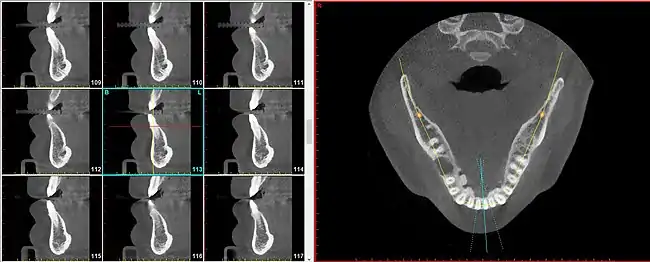

A radial plane is an anatomical plane that is used to describe a virtual slice along a radius of a somewhat cylindrical shaped body part.[1] The radial planes need not be perfectly drawn to overlap on an exact intersection point, particularly when the body part being sectioned is not a perfect cylinder, such as in the case of the maxilla and mandible.

The radial plane can be useful because certain anatomical elements repeat in a circumferential manner (such as around the curvature of the dental arch (i.e. the jaw) and to speak of these entities using parallel planes becomes cumbersome and inaccurate.

For instance, the segment of bone on the outer circumference of each individual tooth is referred to as the facial plate of bone. Because the facial plate of bone is anterior to the incisors (in the front of the mouth) but lateral to the premolars and molars (in the back of the mouth), to visualize the facial plate of bone on various teeth will require sagittal slices for the former but coronal slices for the latter. To achieve greater uniformity and diminished confusion, simply speaking of radial slices provides a satisfactory solution for all teeth in both (upper and lower) arches.